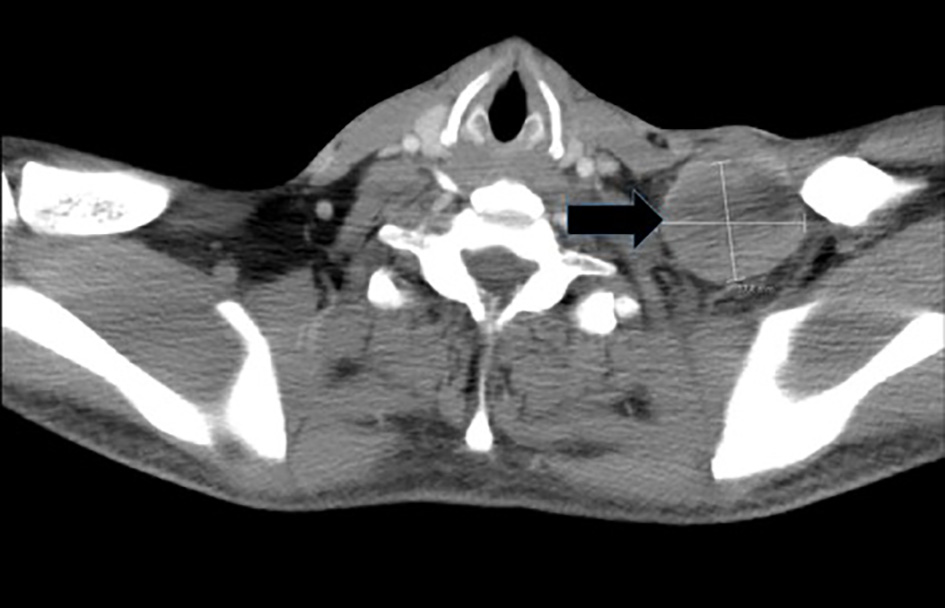

Magnetic resonance imaging (MRI) of the spine reported an epidural mass at T12-L1 level with spinal canal stenosis at T12 level (Fig. 1). Further workup included CT of chest/abdomen and pelvis which showed a large anterior mediastinal mass measuring 8.4 × 5.9 cm (Fig. 2), mixed lytic/sclerotic bony lesions in the spinal bodies from T10 to L1 (Fig. 3), the iliac crests, left sacrum, and the left ischial tuberosity and left supraclavicular lymphadenopathy (Fig. 4). The differential at that time inclined towards germ cell tumor and lymphoma and decision was made to biopsy the left supraclavicular fossa lymph node.

Figure 1. MRI spine depicting the lytic destruction of the spinal bodies and epidural mass at level T12-L1.